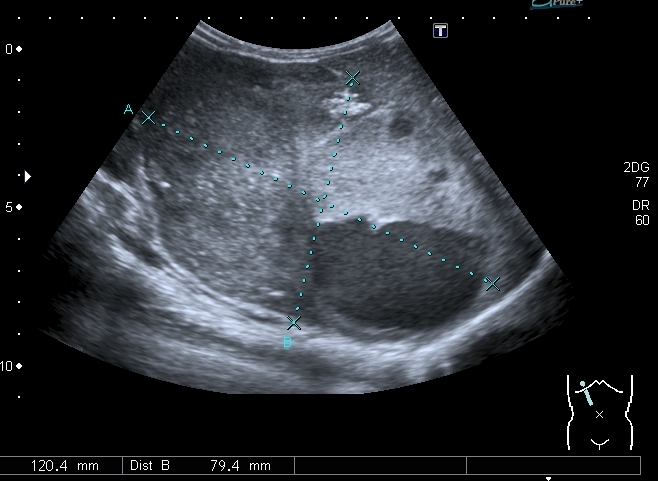

При УЗИ вся правая половина живота выполнена солидно - кистозным образованием больших размеров.

Правая почка нашлась в полости таза, верхним полюсом прилежала к образованию, но не была с ним связана.

Направлен в онкогематологический центр, диагноз нейробластомы из правого надпочечника верифицирован морфологически.